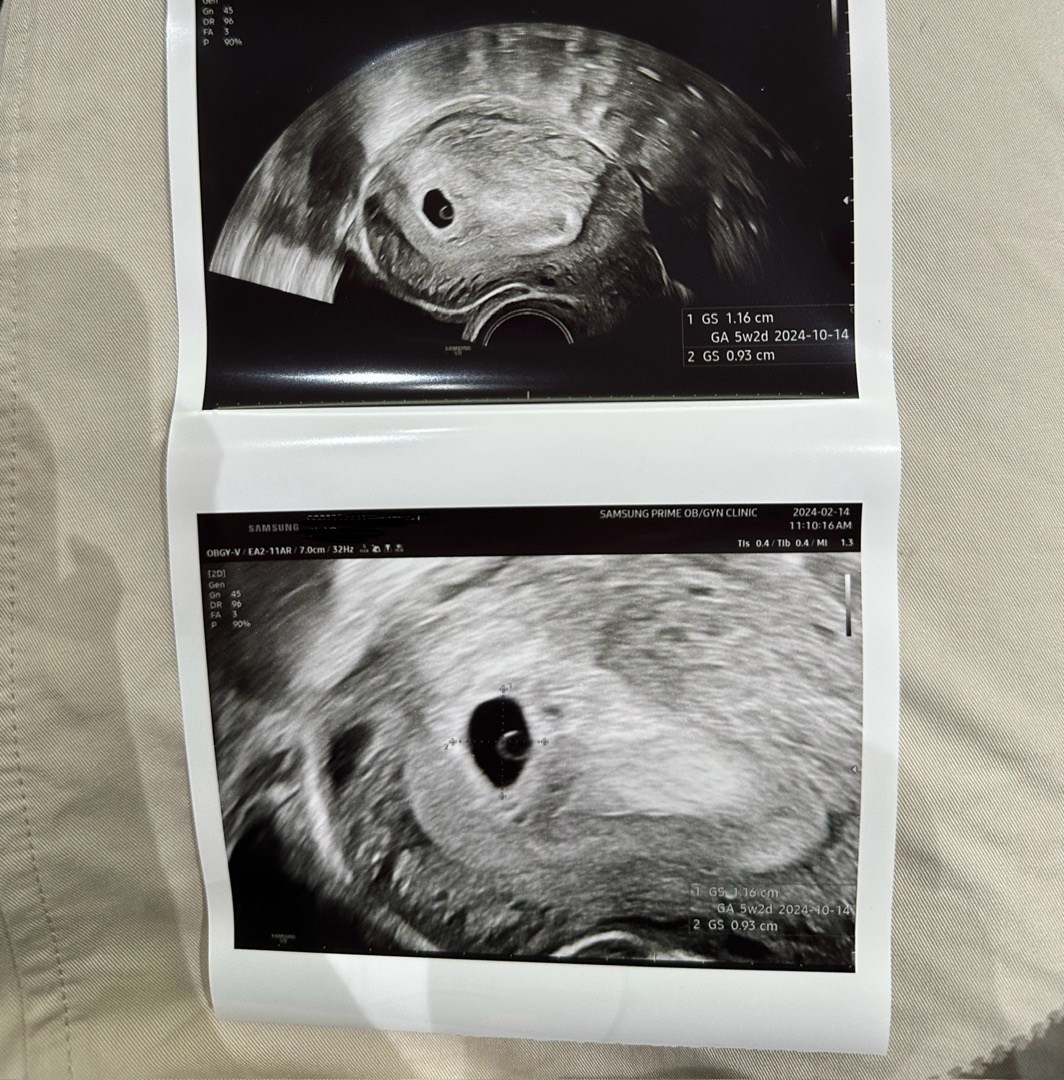

5주차 첫 아기집보고왔어요 🪽🤍

보러가기전까지만해도 자리는 잘잡았을까..아기집모양은 괜찮을까 걱정이 이만저만아니였는데, 모양도 너무 동그랗고 난황도 눈에 너무 잘보여서 행복하네요.. 🥰 2주뒤에 아기가 보일거라고 그때보자는데 또 아가가 잘 커있을지 걱정시작입니다 ㅎ 다들 이렇게 매주 걱정이시겠죠.. 휴 🥹 🤍